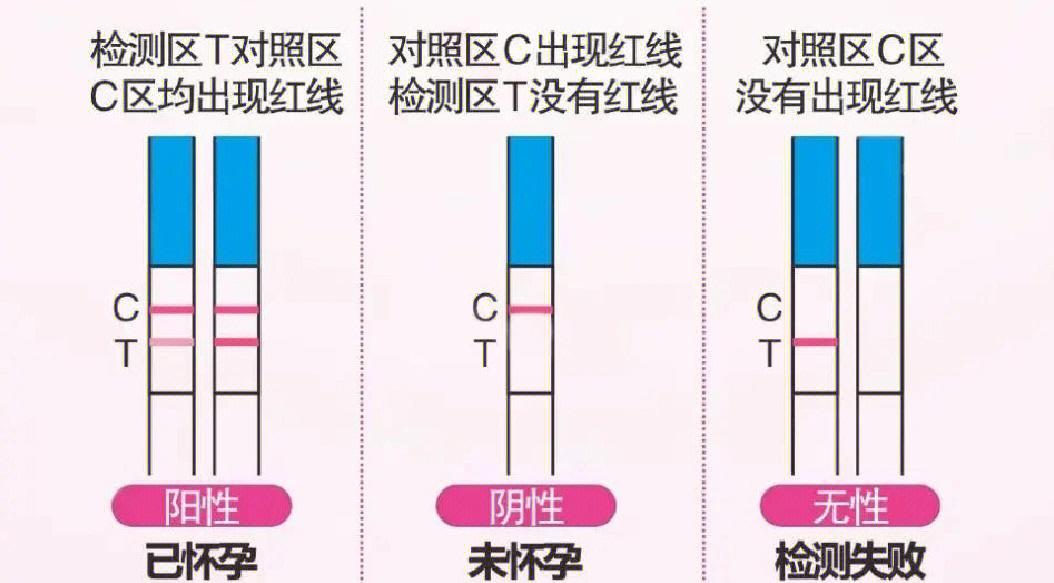

早早孕一深一浅是怀孕了吗?..

应该是了,弱阳性你测的比较早再晚几天再测就深了;早早孕试纸一深一浅可能由以下原因导致1 怀孕时间较短早早孕试纸通过检测尿液中人绒毛膜促性腺激素hCG的水平判断是否怀孕若怀孕时间较短如受孕后710天,hCG浓度可能未达...